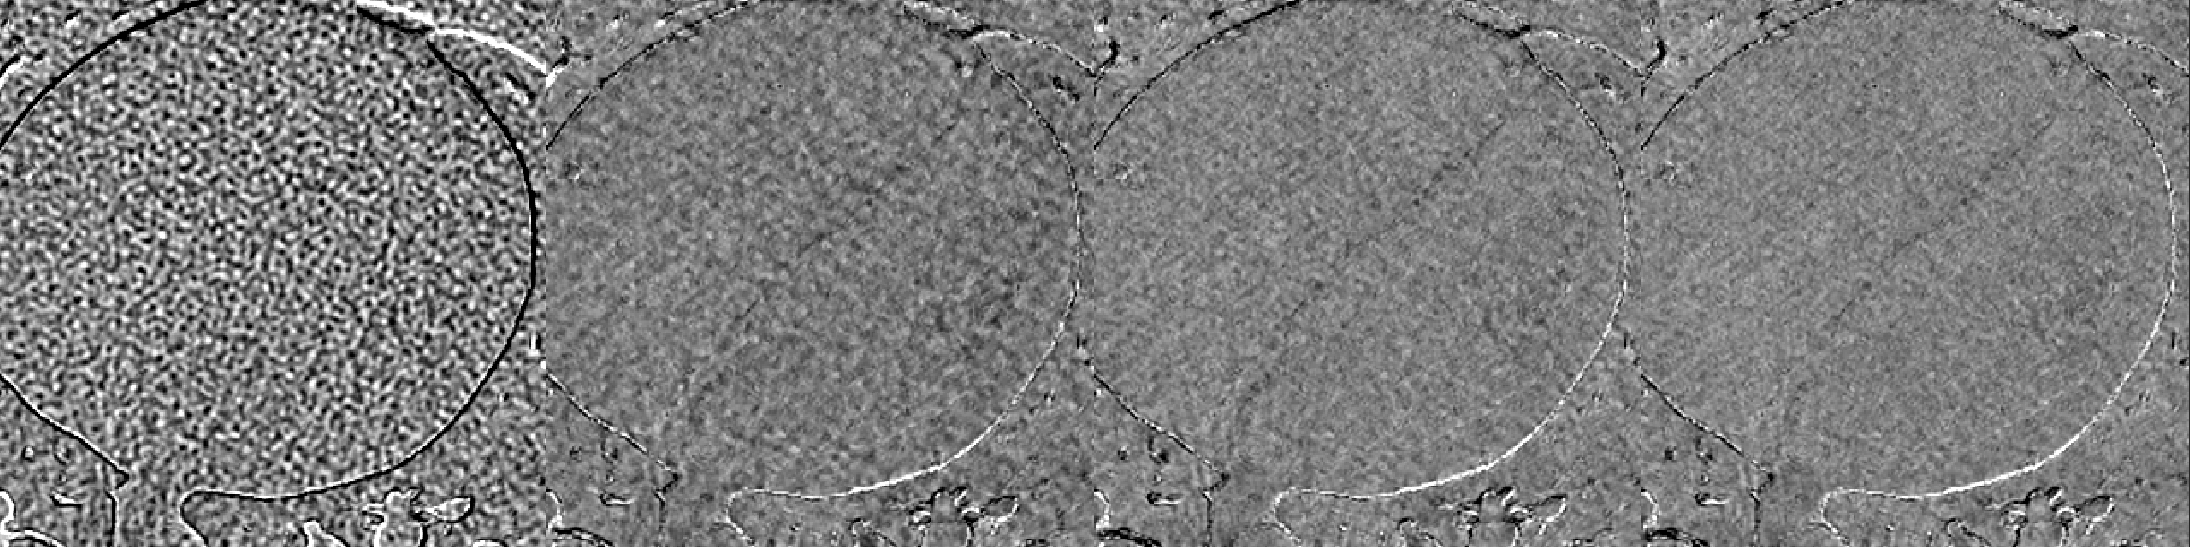

A cardiac FBP image was inferenced on the trained DL-MBIR network. Inference time for every network was between 4 and 6 seconds, and it goes up with the increase in the number of input channels. The MBIR version of the same exam was also available. Figure 3 shows a comparison, for 4 slices – LABEL:sub@fig:Image_10, LABEL:sub@fig:Image_50, LABEL:sub@fig:Image_90, and LABEL:sub@fig:Image_170 in the image volume, among MBIR image, FBP image, and the outputs of DL-MBIRZ𝐷𝐿-𝑀𝐵𝐼subscript𝑅𝑍DL\text{-}MBIR_{Z}, where Z=1, 3, 5𝑍135Z=1,\ 3,\ 5. Figure 4 shows a comparison, for the same slices in the image volume, among difference between images and the MBIR images. Figure 5 has a profile plot to show the comparison of DL-MBIRZ𝐷𝐿-𝑀𝐵𝐼subscript𝑅𝑍DL\text{-}MBIR_{Z} and FBP images w.r.t the MBIR images.

Figure 3: Reconstructed image. (left to right): MBIR𝑀𝐵𝐼𝑅MBIR, FBP𝐹𝐵𝑃FBP, DL-MBIR1𝐷𝐿-𝑀𝐵𝐼subscript𝑅1DL\text{-}MBIR_{1}, DL-MBIR3𝐷𝐿-𝑀𝐵𝐼subscript𝑅3DL\text{-}MBIR_{3}, DL-MBIR5𝐷𝐿-𝑀𝐵𝐼subscript𝑅5DL\text{-}MBIR_{5}. LABEL:sub@fig:Image_10, LABEL:sub@fig:Image_50, LABEL:sub@fig:Image_90 and LABEL:sub@fig:Image_170 represent different slices in the image volume. WW/WL 450/0 HU.

Visually, all DL-MBIR images bear close resemblance to the MBIR images in figure 3. It is confirmed by the difference images in figure 4. In the profile plot of Figure 5, the DL-MBIR profiles closely follow that of MBIR.